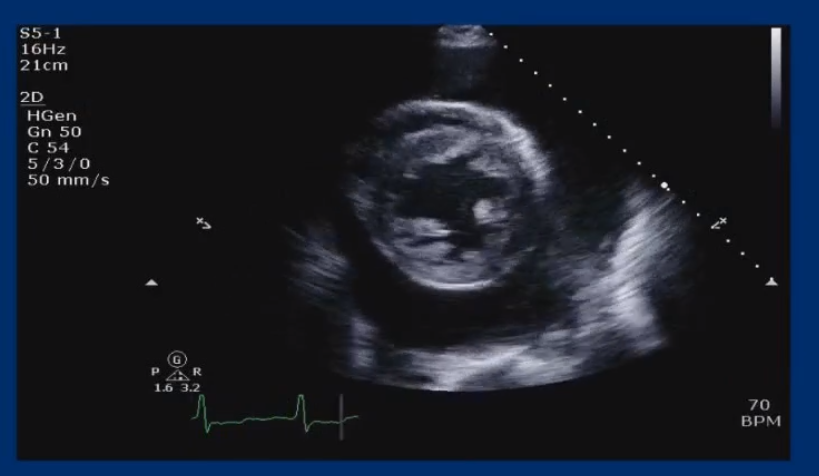

Explore real echocardiography case studies that provide practical insights and enhance your diagnostic skills.

Engage in learning experience using high-quality images to reinforce your knowledge and improve your diagnostic accuracy.

Welcome to the ultimate resource for those seeking to boost their echocardiography skills through in-depth case studies and real images. Dive into our cases studies and images designed to address your learning needs and elevate your diagnostic proficiency. Join us and unlock the echo tips and tricks and take your skills to the next level.

Fetal Echocardiography Images

PDA Aneurysm (Fetal/TTE Comparison)

Vascular Ring

Hypoplastic Left Heart Syndrome